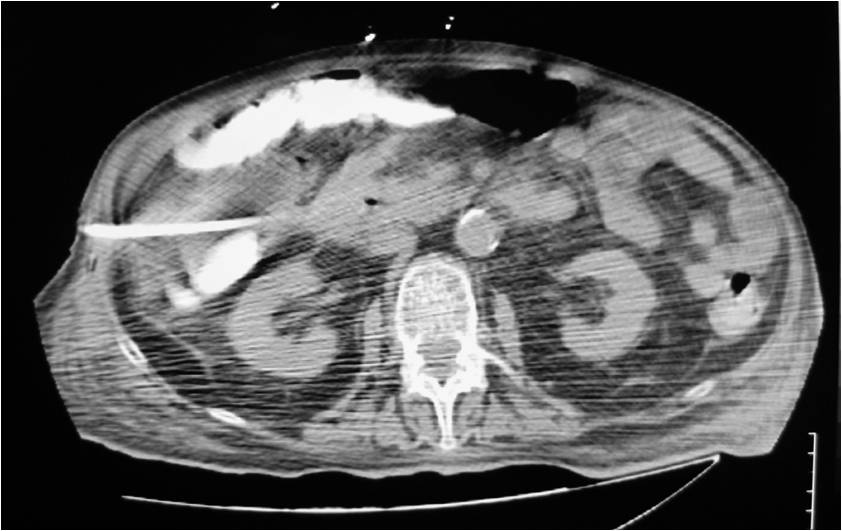

- Large abdominal abscess post- pancreatic surgery

- Successful drainage